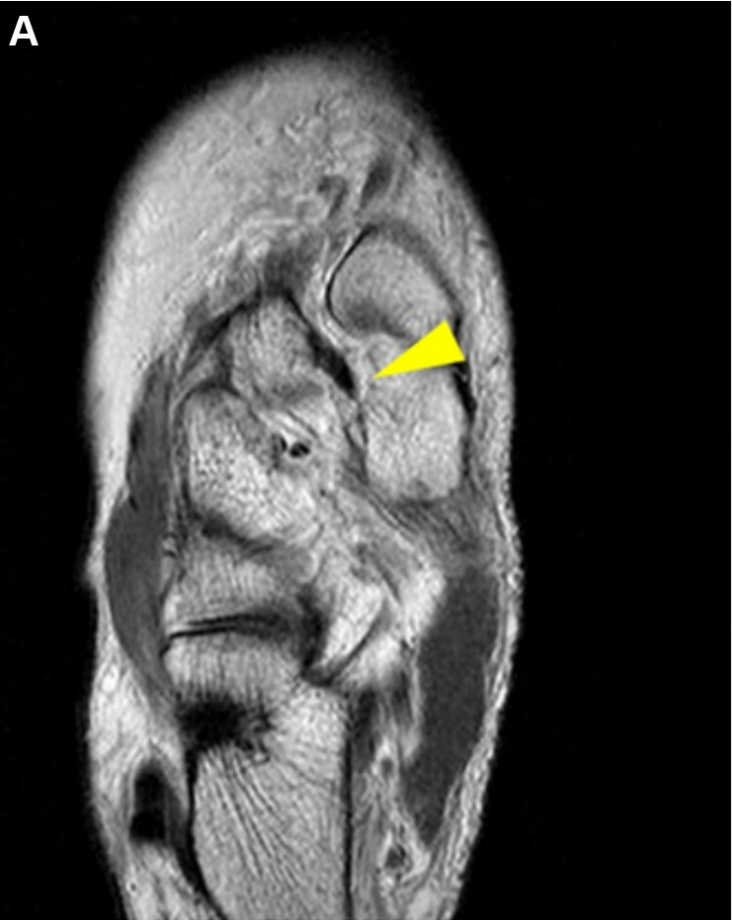

▲图示术前Lisfranc韧带的磁共振成像(MRI)评估:可见Lisfranc韧带断裂(黄色箭头标记)。